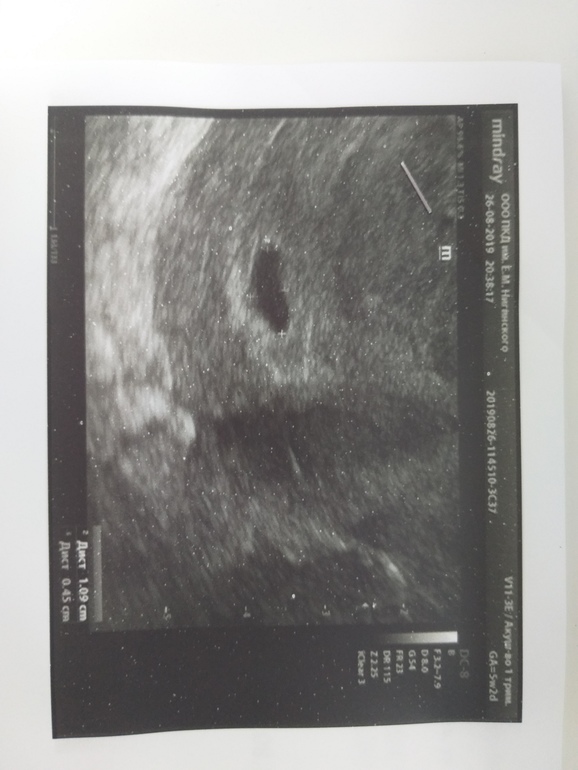

Случилась одна замершая беременность - анембриония . Диагноз - хронический аутоиммунный эндометрит . Назначили визанну, начала пить с 1 дм .

Отмена визанны и дюфастон После лапароскопии кисты яичника выписали визанну на длительный . . . Задержка 3 месяца 16 .05 .2019 г . у меня была замершая беременность и случился выкидыш . . . .